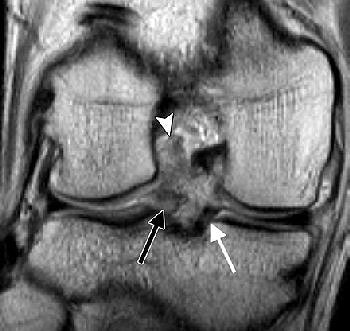

![]() |

| LMRT and meniscus extrusion in a 20-year-old man with ACL tear. Above, coronal posterior and midknee (below) intermediate-weighted (4083/17) fast SE MR images of the right knee show ACL tear (arrowhead), LMRT (black arrow), and normal medial meniscus root (thin white arrow). The distance between the two vertical lines in image below indicates meniscus extrusion of 3.7 mm (thick white arrow). |